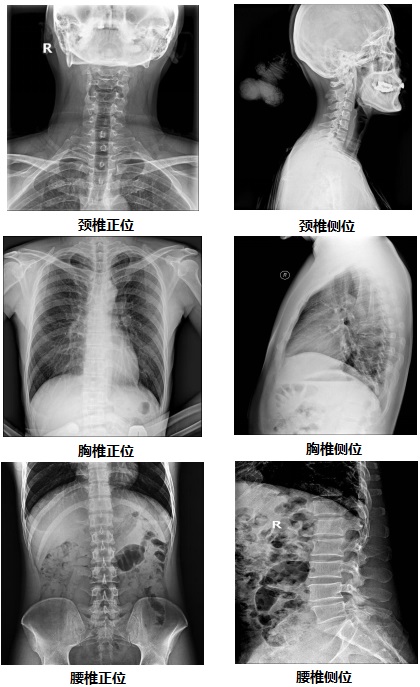

【固定懸吊dr-PLD7800E部分臨床效果圖】